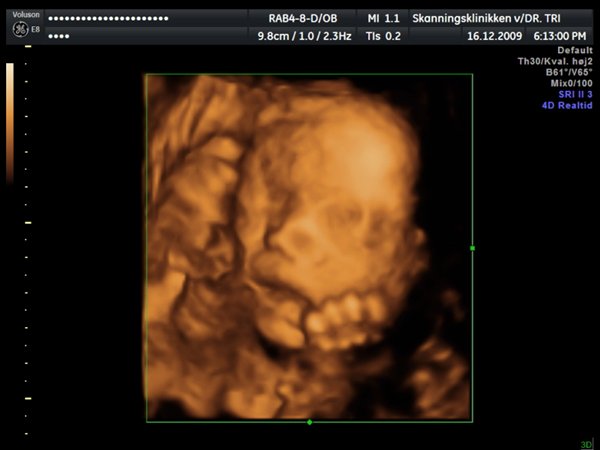

Ja, så var vi til 3D scanning med Ida igår. Og hvad kan jeg sige andet end hun er en meget træt pige

Jeg tror vi talte hun gabte mellem 10 og 11 gange under hele scanningen. Derudover havde hun meget travl med at gemme sig bag sine hænder som hun hele tiden åbnede og lukkede så det så ud som om hun vinkede

Billederne blev ikke så gode som jeg havde håbet, for lige som sin bror ligger hun meget tæt på moderkagen og med navlestregnen forand hovedet. Men de er ok, vi kan da se at hun ser sund og rask ud og at hun trives derinde.

Vedhæftede fotos (klik for at se i fuld størrelse)